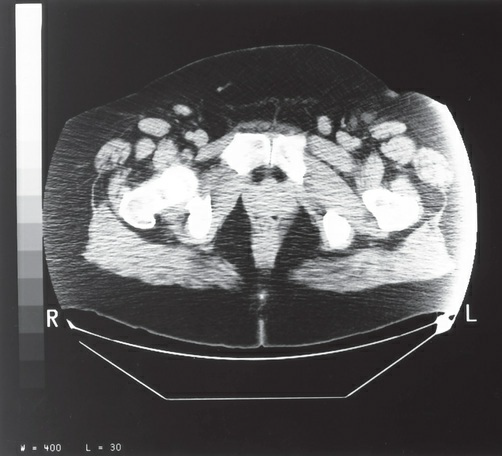

The artifact present on the lateral borders of the image in the

figure most likely represents which of the following?

a. edge gradient

b. out-of-field artifact

c. tube arcing

d. beam hardening

out-of-field artifact

The image in the figure was produced using the following

parameters: large (full) scan field of view (SFOV); maximum

display field of view (DFOV) (48 cm); 200 mA, 120 kVp; soft

tissue algorithm. Which of the following technical adjustments

would serve to reduce the artifact present?

a. switching to a detail or bone algorithm

b. using a smaller SFOV

c. increasing the mA to 240 and the kVp to 140

d. centering the patient within the SFOV

centering the patient within the SFOV

The region of interest (ROI) measurement in the figure

provides an average density of +1.9 HU. This material is most

likely:

a. fat

b. blood

c. tumor

d. water

water

The image in the figure was most likely displayed with the use

of which of the following window widths?

a. 70

b. 400

c. 1300

d. 3800

400